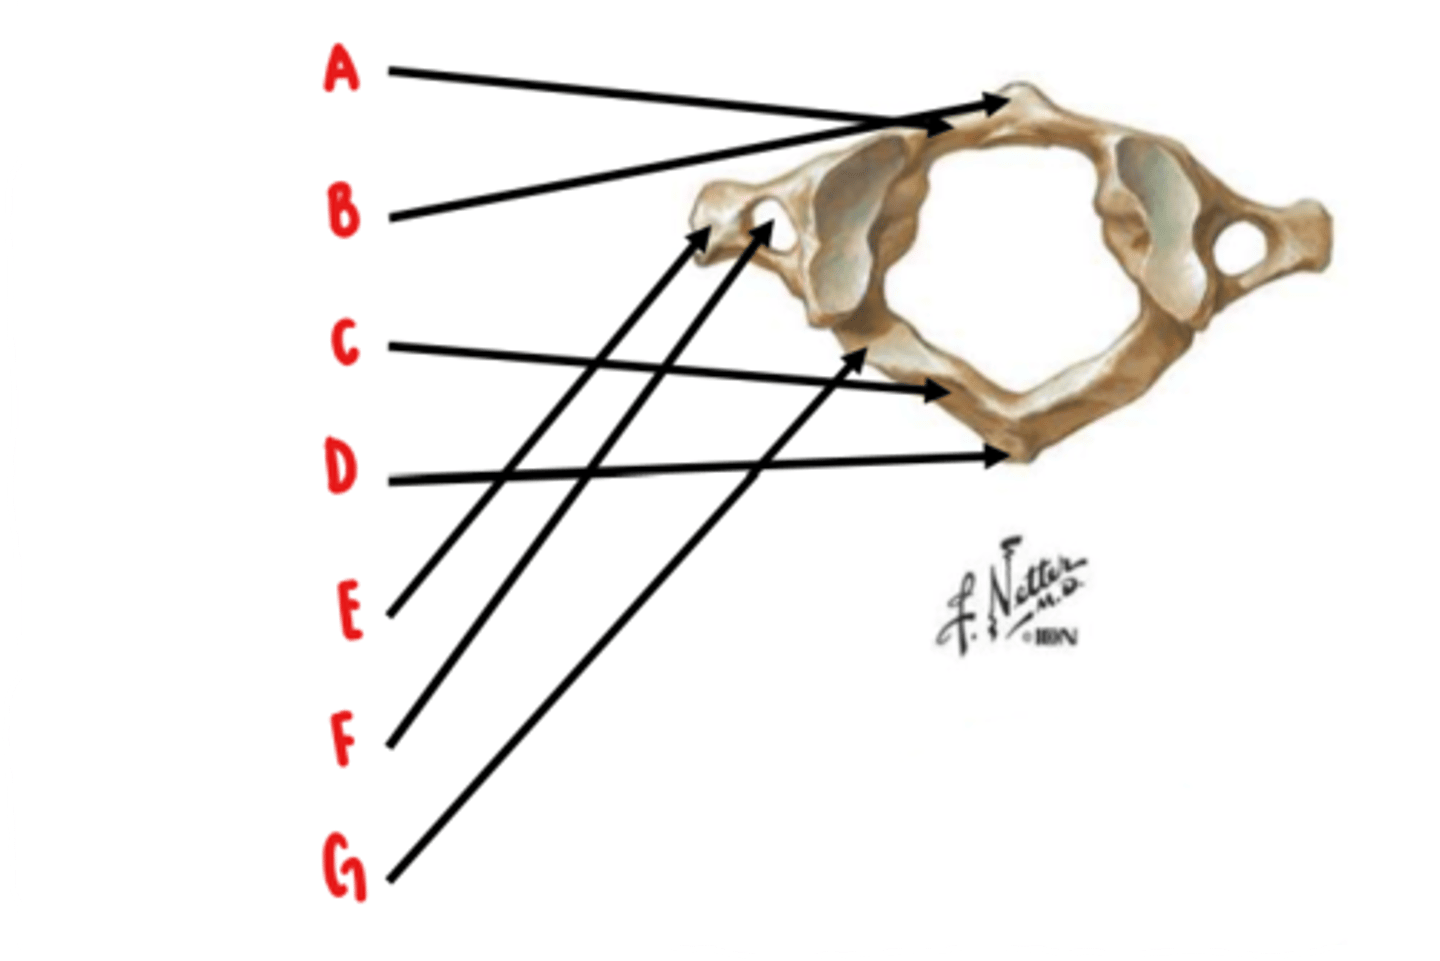

Atlas (C1)

What vertebrae is this?

anterior arch

Identify A

anterior tubercle

Identify B

posterior arch

Identify C

posterior tubercle

Identify D

transverse process

Identify E

transverse foramen

Identify F

groove for vertebral artery

Identify G